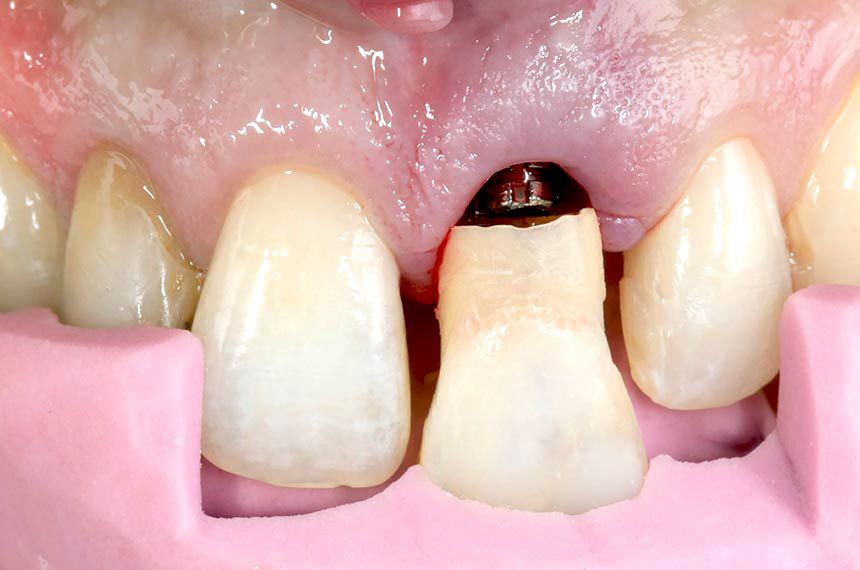

The patient, a 29 year-old Caucasian woman, non-smoker in good general health, was referred to the author’s private dental office with symptoms of vertical root fracture on the maxillary left central incisor (Fig. 1). There was no significant bone loss. The maxillary left central incisor had a history of periapical surgery and endodontic retreatment (Fig. 2). Patient’s oral hygiene was fair. The patient’s history showed no pathological findings and no contraindications with regard to dental implant therapy. The patient has a high lip position that exposes the gingiva so her expectations with regard to the esthetics of the treatment outcome were very high (Fig. 3). It was decided that the maxillary left central incisor should be replaced by an immediate implant.

Following administration of local anesthesia, atraumatic tooth extraction was accomplished without flap reflection to preserve the interproximal papillae and the remaining buccal and lingual plates of bone. The extraction socket was carefully examined for dehiscences and fenestrations and debrided of residual periodontal fibers using curettes. Following socket debridement, a Straumann Bone Level Tapered Implant (Regular CrossFit™ Connection Ø 4.1mm, SLA® 14mm) was placed in tooth position 21 (FDI) (Fig. 4). A surgical guide was used to help ensure ideal three-dimensional placement (Fig. 5). The implant showed adequate initial stability when placed with a torque driver at 35 Ncm. A customized provisional titanium cylinder (Temporary Abutment) was then placed and hand-tightened onto the implant and trimmed using a positioned guide to ensure the correct height (Fig. 6). The hollowed crown of the extracted tooth was relined with acrylic resin and adapted to the custom provisional abutment using a positioned guide to ensure exact positioning (Figs. 7, 8). The provisional shell was precisely finished with composite resin on the temporary abutment to recreate the cervical emergence of the extracted tooth (Fig. 9). A synthetic bone graft substitute (Straumann BoneCeramic) was placed between the buccal plate of bone and the implant in order to fill the space and maintain the soft tissue contour. After immediate implant placement and bone augmentation, a supraperiosteal envelope was made labial to the socket. These tunnels, used to accommodate the connective tissue graft, were dissected sharply with a microsurgical blade (Fig 10). Care was taken to leave the periosteum attached to the bone during dissection. A connective tissue graft from tuberosity was inserted into the prepared envelope space and secured with non-resorbable sutures (Fig. 11). The immediate provisional restoration was tightly screwed onto the implant by hand. The provisional restoration was adjusted to clear all contacts in centric occlusion and during eccentric movements. A periapical radiograph was obtained to ascertain the fit of the provisional restoration (Fig. 12).